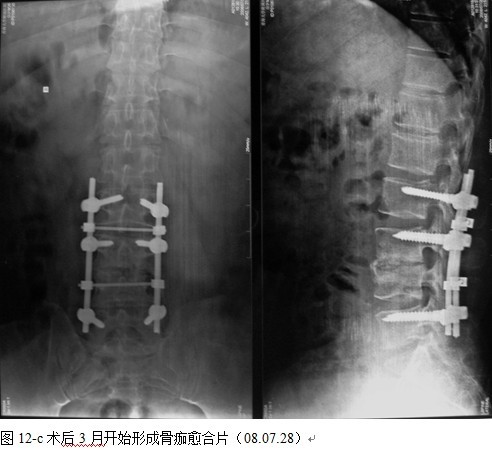

本组手术用时间3~4h , 平均3.5h 。术中出血300~500ml , 平均约350ml 。术后症状完全缓解,无神经功能障碍加重等并发症,1例营养差的老年患者伤口出现窦道,1例因肝功能差,术后未口服抗痨药,伤口出现窦道,经换药后二期愈合,其余病例伤口均一期愈合。马尾神经受损的患者术后基本恢复正常。术后一周后凸角平均 5.4°后凸畸形平均矫正90%以上, 最终后凸角平均8.3°,后凸角度平均丢失4.2°。随访3个月有87%(40/46)有骨痂形成,6个月91.3%(42/46)明显骨性愈合(见图),其余4例9-12个月内愈合,随访时间3-32个月,平均11个月,46例患者中2例在术后2个月和3个月时背部形成脓肿,换药后治愈。2例出院1月后并发结核性脑膜炎,治疗后好转。1例因椎弓根钉偏外,刺激神经根,5个月后从侧方脱出,疼痛加重,因前后路植骨完全愈合,取出后症状完全缓解。